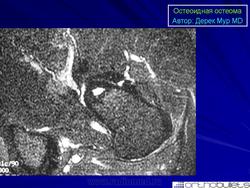

(а) МР изображение фиксирует очаг - стрелка в шейке правой бедренной кости с окружающим отеком (*) костного мозга. Имеет место некоторое количество выпота.

(б) МР изображение (с гадолинием) регистрирует очаг - стрелка и интенсивный синовиальный компонент - наконечники стрел.

Внутрисуставная остеоид остеома мыщелка бедренной кости у 29-летнего мужчины.

(а) Боковая рентгенограмма коленного сустава регистрирует очаг - стрелка в области мыщелка бедренной кости.

(б) МР изображение – очаг с низким уровнем «сигнала», с центральным очагом - стрелка.